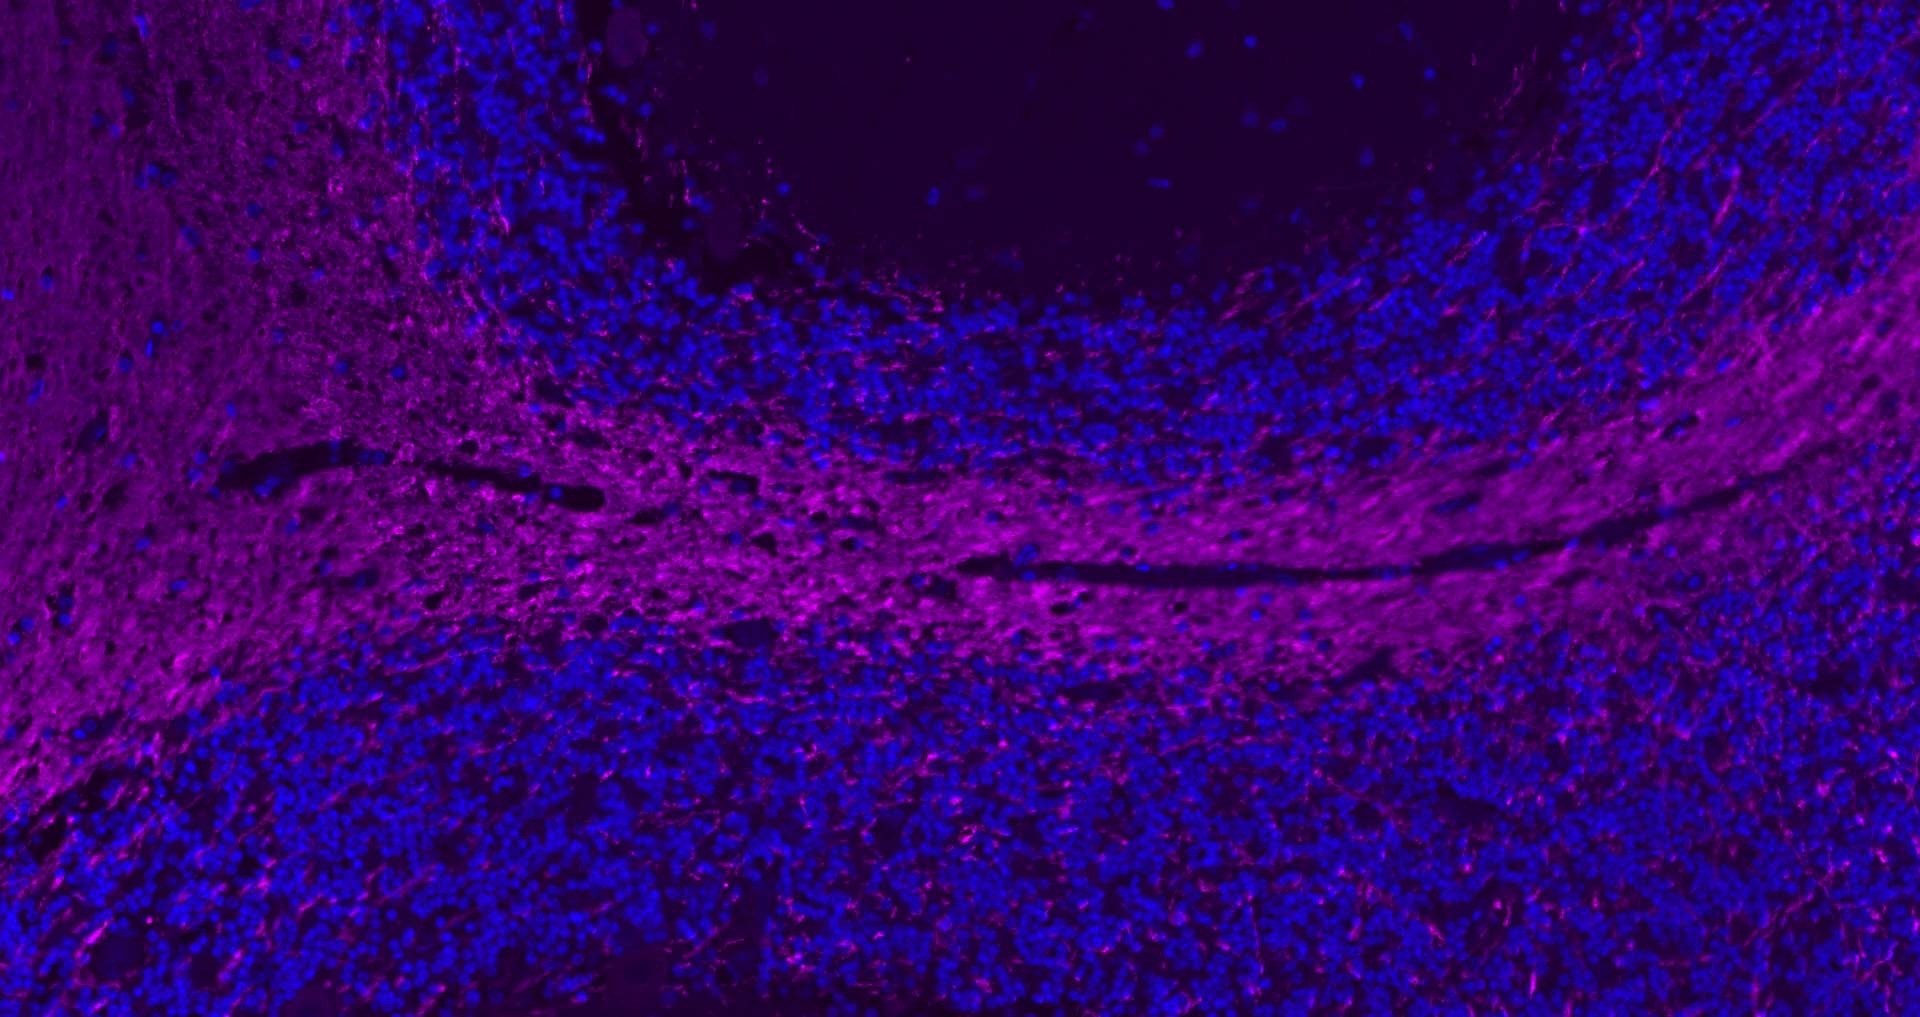

| Verified Activity | 1. Paraformaldehyde-fixed, paraffin embedded Rat Cerebellum; Antigen retrieval by boiling in sodium citrate buffer (pH6.0) for 15 min; Antibody incubation with MBP Polyclonal Antibody, Unconjugated at 1:200 overnight at 4°C. Followed by conjugated Goat Anti-Rabbit IgG antibody (Purple, TMAB-02007C5), DAPI (blue) was used to stain the cell nuclei.

2. Paraformaldehyde-fixed, paraffin embedded Human Cerebellum; Antigen retrieval by boiling in sodium citrate buffer (pH6.0) for 15 min; Antibody incubation with MBP Polyclonal Antibody, Unconjugated at 1:200 overnight at 4°C. Followed by conjugated Goat Anti-Rabbit IgG antibody (Purple, TMAB-02007C5), DAPI (blue) was used to stain the cell nuclei. 3. Paraformaldehyde-fixed, paraffin embedded Human Left Parietal Lobe; Antigen retrieval by boiling in sodium citrate buffer (pH6.0) for 15 min; Antibody incubation with MBP Polyclonal Antibody, Unconjugated at 1:200 overnight at 4°C. Followed by conjugated Goat Anti-Rabbit IgG antibody (Purple, TMAB-02007C5), DAPI (blue) was used to stain the cell nuclei. 4. Paraformaldehyde-fixed, paraffin embedded Mouse Cerebrum; Antigen retrieval by boiling in sodium citrate buffer (pH6.0) for 15 min; Antibody incubation with MBP Polyclonal Antibody, Unconjugated at 1:200 overnight at 4°C. Followed by conjugated Goat Anti-Rabbit IgG antibody (Purple, TMAB-02007C5), DAPI (blue) was used to stain the cell nuclei. 5. Paraformaldehyde-fixed, paraffin embedded Mouse Cerebellum; Antigen retrieval by boiling in sodium citrate buffer (pH6.0) for 15 min; Antibody incubation with MBP Polyclonal Antibody, Unconjugated at 1:200 overnight at 4°C. Followed by conjugated Goat Anti-Rabbit IgG antibody (Purple, TMAB-02007C5), DAPI (blue) was used to stain the cell nuclei. 6. Paraformaldehyde-fixed, paraffin embedded Human Duodenum; Antigen retrieval by boiling in sodium citrate buffer (pH6.0) for 15 min; Antibody incubation with CHGA Polyclonal Antibody, Unconjugated at 1:200 overnight at 4°C. Followed by conjugated Goat Anti-Rabbit IgG antibody (Purple, TMAB-02007C5), DAPI (blue) was used to stain the cell nuclei. 7. Paraformaldehyde-fixed, paraffin embedded Human Fundus; Antigen retrieval by boiling in sodium citrate buffer (pH6.0) for 15 min; Antibody incubation with CHGA Polyclonal Antibody, Unconjugated at 1:200 overnight at 4°C. Followed by conjugated Goat Anti-Rabbit IgG antibody (Purple, TMAB-02007C5), DAPI (blue) was used to stain the cell nuclei. 8. Paraformaldehyde-fixed, paraffin embedded Mouse Stomach; Antigen retrieval by boiling in sodium citrate buffer (pH6.0) for 15 min; Antibody incubation with CHGA Polyclonal Antibody, Unconjugated at 1:200 overnight at 4°C. Followed by conjugated Goat Anti-Rabbit IgG antibody (Purple, TMAB-02007C5), DAPI (blue) was used to stain the cell nuclei. 9. Paraformaldehyde-fixed, paraffin embedded Mouse Small Intestine; Antigen retrieval by boiling in sodium citrate buffer (pH6.0) for 15 min; Antibody incubation with CHGA Polyclonal Antibody, Unconjugatedat 1:200 overnight at 4°C. Followed by conjugated Goat Anti-Rabbit IgG antibody (Purple, TMAB-02007C5), DAPI (blue) was used to stain the cell nuclei. 10. Paraformaldehyde-fixed, paraffin embedded Rat Cerebrum; Antigen retrieval by boiling in sodium citrate buffer (pH6.0) for 15 min; Antibody incubation with NF-L Polyclonal Antibody, Unconjugated at 1:200 overnight at 4°C. Followed by conjugated Goat Anti-Rabbit IgG antibody (Purple, TMAB-02007C5), DAPI (blue) was used to stain the cell nuclei. ![]() ![]() ![]() ![]() ![]() ![]() ![]() ![]() ![]() ![]() |